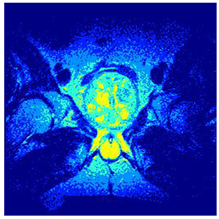

In this subsection, we will discuss the experiment designed to evaluate the performance of EO with cross-entropy for the segmentation of prostate MRI images. To this end, we use a group of reference images formed by a set of six prostate MRI images; see Figure 4. All the images from the group were extracted from the Ferenc Jolesz National Center for Image-Guided Therapy, Harvard Medical School, or Brigham Health Hospital datasets with no additional preprocessing [50]. Prostate MRI images are primarily used for disease diagnosis or to establish treatment for prostate-related diseases such as prostatitis, benign prostatic hyperplasia (BPH), and prostate cancer, among other diseases or medical conditions. In the context of this article, the images were used to test the efficiency of the equilibrium optimizing algorithm and compare it with the other six chosen algorithms. The segmentation of MRIs is carried out over four different thresholds levels: = 3, 4, 5, and 8. Due to the nature of the images, there was a limited number of different tissues in the images; thus, there was no point in evaluating a larger number of .

Figure 4.

Eleven transaxial-cut prostate MRI images. This figure presents a set of eleven transaxial-cut magnetic resonance (MR) images of the prostate. These images serve as the input dataset for evaluating the segmentation performance of the proposed algorithm.

Table 5 presents the segmentation of the MRIs using EO for a qualitative inspection. From Figure 5, it is clear that two lumps in the prostate have been highlighted by the thresholding process. Prostatic MRIs present noisy conditions, which makes it difficult to visualize the thresholding with the naked eye, so in Figure 5 we present the thresholded image as well as the histogram with the values of the thresholds generated by the EO. It can be observed in the histogram that the thresholds present an adequate distribution, even though this particular image has impulsive noise and a simple shape. Our findings indicate that four thresholds are typically sufficient for this application, which corresponds to identifying five different tissue types in the image. A smaller threshold value may result in a lack of sufficient contrast to highlight relevant anatomical structures, such as the prostate capsule. In contrast, a higher number of thresholds may lead to the incorrect differentiation of anatomical regions that should be connected.

Table 5.

Segmentation of transaxial-cut prostate MRI images Using EO and cross-entropy. This table presents the segmentation results of transaxial-cut prostate MRI images using the equilibrium optimizer (EO) and cross-entropy. Each row corresponds to a distinct MRI image, while the columns nt represent the number of thresholds applied during segmentation. The results illustrate the performance of the EO algorithm across different threshold levels for each image.